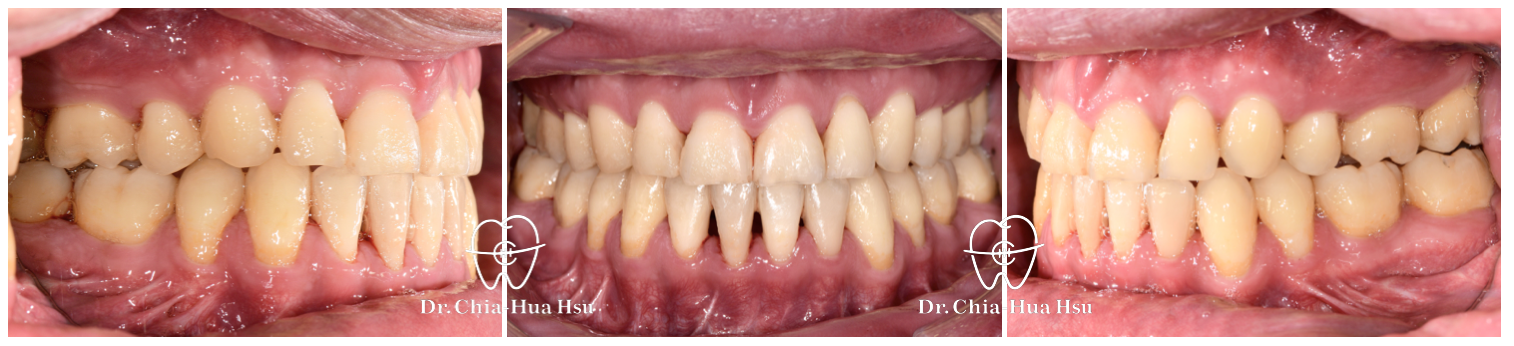

• 有在長期重訓的張先生,年輕時做過矯正,不過因為患者下顎後縮(小下巴)先天構造上呼吸道比較狹窄,隨著年紀漸增以及增肌過程體重增加,進而導致患者出現嚴重的睡眠呼吸中止症,患者嘗試過正壓呼吸器但是戴不住,因而尋求正顎手術治療。

• 病患主訴:下顎後縮、睡眠呼吸中止、二級骨性咬合不正。

• 問題分析:患者是標準的骨骼二類咬合(Skeletal Class II),下巴後縮、有睡眠呼吸中止症以及齒列不正。

• 治療方式:使用傳統金屬矯正器,合併正顎手術(雙顎),以手術方式將下顎骨前移改善呼吸道與外觀。

• 治療時間:2 年 7 個月。

• 治療結果:齒列排齊,睡眠呼吸中止症改善許多,臉型變長、下巴輪廓也較明顯。